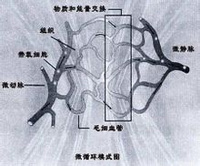

微循环是指微动脉与微静脉之间微血管中的血液循环,是血液与组织细胞进行物质交换的场所。在显微镜下才能加以观察。一般由微动脉、后微动脉、毛细血管前括约肌、真毛细血管、通血毛细血管、动-静脉吻合枝和微静脉七部分组成,是心血管系统与组织细胞直接接触的部分。微循环基本功能是实现物质代换,向各组织细胞输送养料和运走代谢产物。